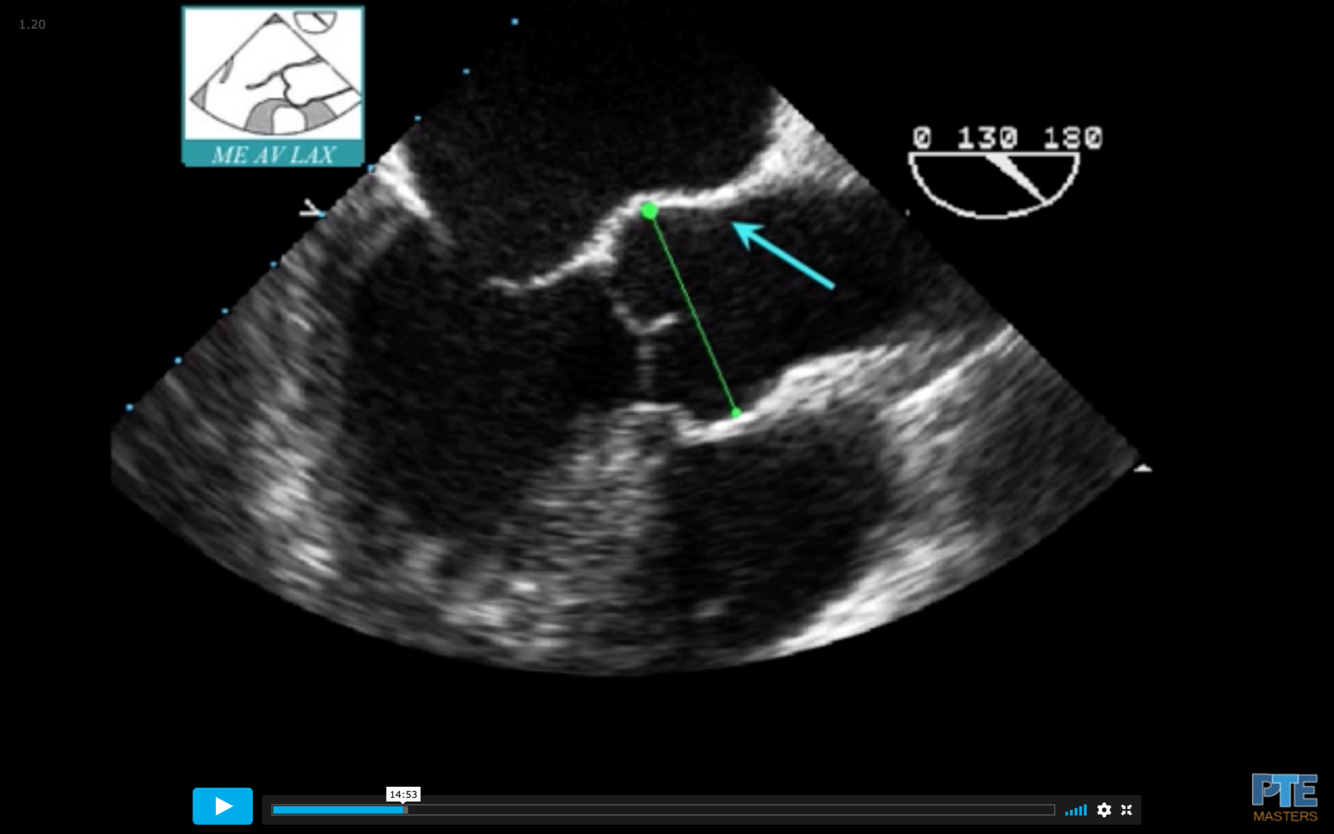

What is the measurement seen here?

Sinus of Valsalva

What is the blue arrow indicating?

Sinotubular Ridge or Sinuotubular Junction

What is the normal size of the Aortic Root in an adult?

What measurement is termed dilated?

Normal = < 40 mm (4.0 cm)

Dilated = >40 mm